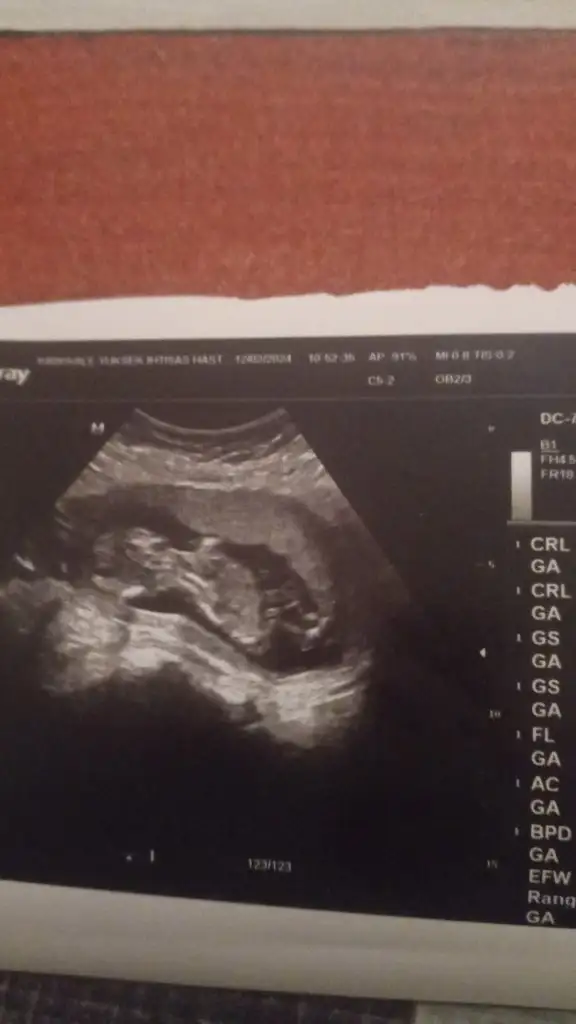

Ben de bakar bakmaz ağa gibi uzanmış bir adam gördüm, ama tamamen totomdan sallıyorumCinsiyet tahmini yapabilir misiniz nolur lütfen ?

Saçları uzun kız saçı gibi. Yoksa anne karnında çocuğun saçı olmuyor mu. Ay ben sallayın diyince abartmış da olabilirim. Annelere soralımMargaret Hale dogadostupanda @Karpuzlu araba @merve

Bence kız.

Tahminlerim doğru çıkarsa bana yazarmısınız